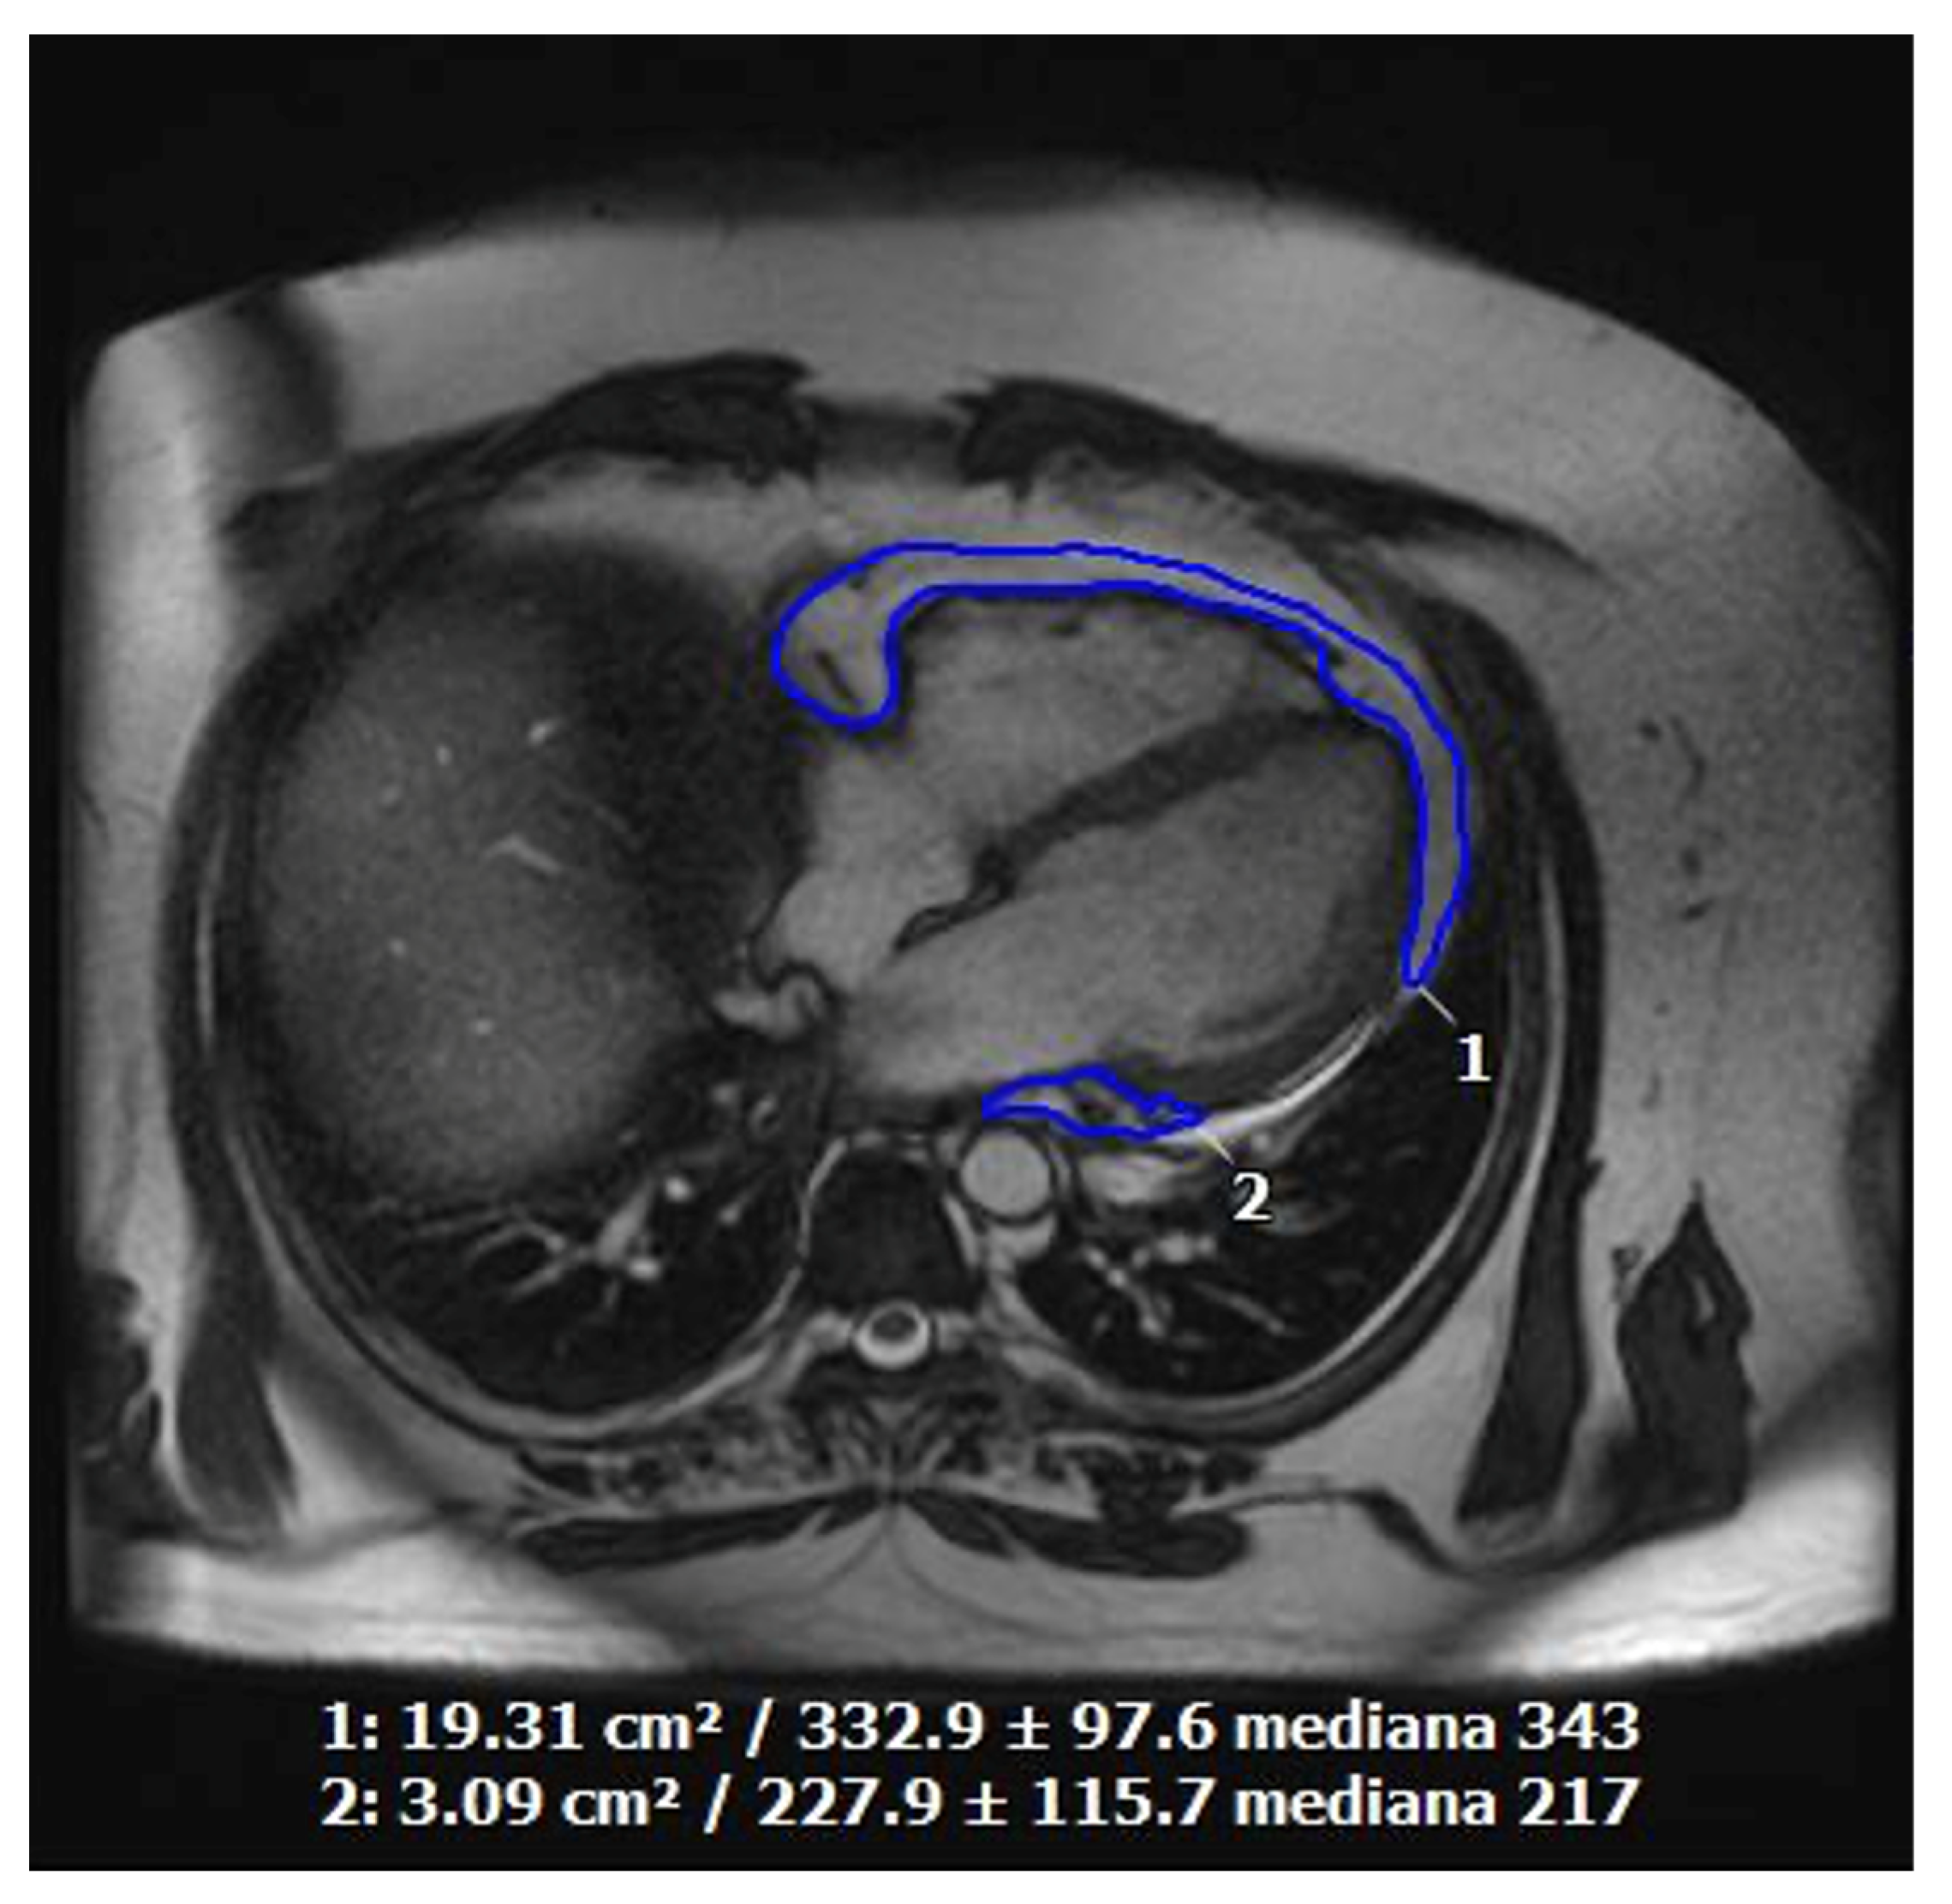

10. Photon-Counting CT and Its Applications in Cardiovascular Diagnostics

11. Cardiac Magnetic Resonance Imaging in Cardiovascular Prevention